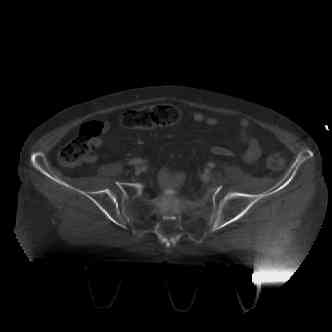

attached are several CT cuts. please let me know if you need more. the CT is pre-pelvic ex-fix placement.

I wouldn't plate the front.

But I would add screws posteriorly.